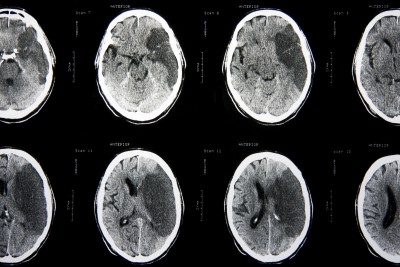

בבית החולים יש לעבור בדיקת ct מוח. הבדיקה נדרשת על מנת לאבחן את סוג האירוע המוחי, איסכמי או המורגי. ככל שמדובר באירוע אסכמי, בטווח של עד 3 שעות מקרות האירוע ניתן לתת תרופה הנקראת TPA. התרופה ניתנת בזריקה לווריד ותפקידה להמיס את קריש הדם.